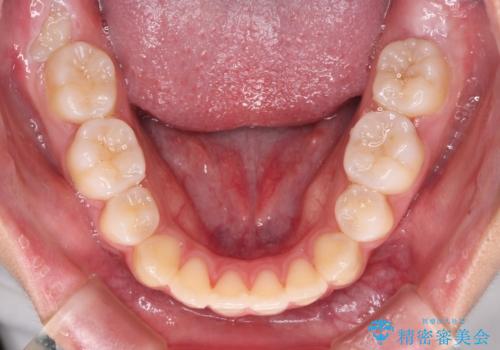

当初は八重歯やデコボコが一番気になっていましたが、抜歯矯正により口元の突出感が改善されるにつれ、口の閉じやすさを実感するようになってきました。

部活動で調整来院に来られないことがしばしばあり、期間は予定よりもかかりましたが、きれいに仕上げることができました。